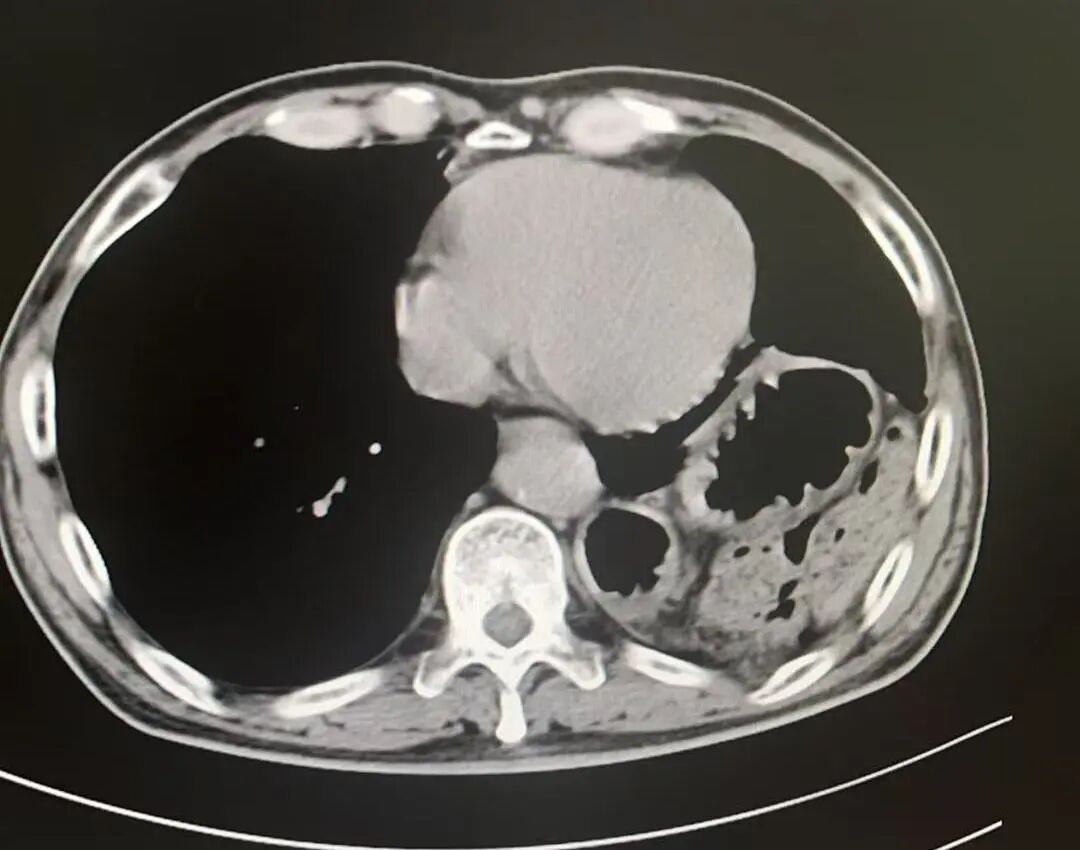

術(shù)中發(fā)現(xiàn)胃、結(jié)腸、小腸及脾臟疝入胸腔且與周圍組織嚴重粘連,部分臟器難以通過微創(chuàng)完全復位。孫振教授果斷決策,通過10厘米切口精細分離粘連,成功還納全部臟器并牢固修補缺損,杜絕復發(fā)隱患。

術(shù)后影像

膈疝修補如拆“定時炸彈”,需松解粘連、歸位臟器、修復缺損三步精準到位。團隊采用階梯策略,在確保手術(shù)效果的同時最大程度降低風險、減少創(chuàng)傷。術(shù)后,劉大爺?shù)陌Y狀迅速緩解,現(xiàn)已康復出院,重歸正常生活。